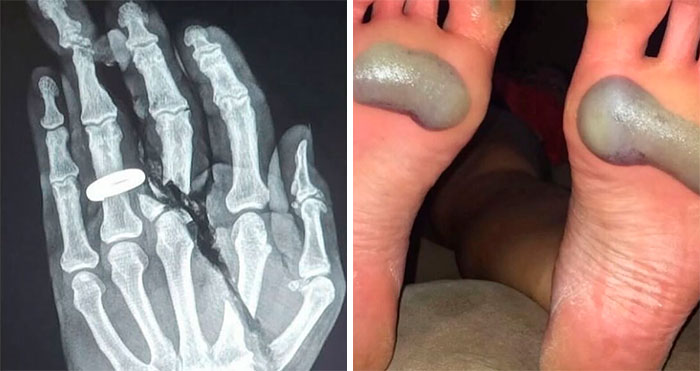

Shelly Fourer 36Kviews 52 50 People Share Their Injuries That Are Not Funny But You Can’t Help But Laugh Interview With Expert